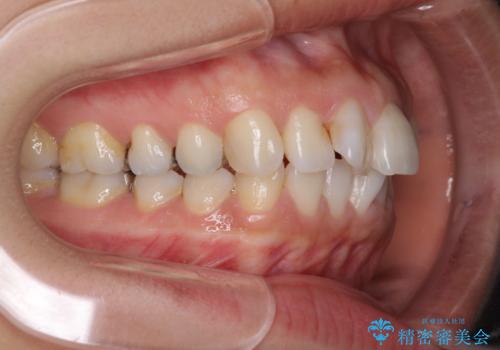

前歯の突出を軽減 インビザラインによる抜歯矯正

- 上の前歯の捻じれと突出感を気にして来院された患者様です。

目立たない装置を希望とのことで、上顎左右第一小臼歯を抜歯し、インビザラインにて矯正治療を行うこととしました。

インビザラインにて抜歯矯正を行うと、高頻度で奥歯が咬み合わなくなります。

抜歯スペースが閉じてからも咬みにくさ改善のためマウスピース矯正を継続するため、治療期間は長期化します。